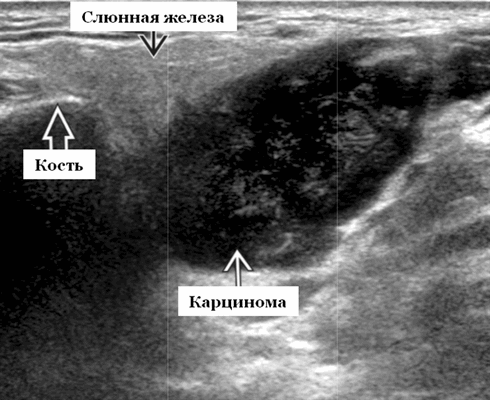

Данные УЗИ слюнных желез при карциноме

- Увеличенное солидное образование околоушной при ультразвуковом сканировании (примерно 75%) или поднижнечелюстной железы (примерно 25%)

- Особенности визуализации неспецифические

- Нечеткие или четко определенные границы.

- Гипоэхогенная, гомогенная или гетерогенная эхоструктура на УЗИ

- Отмечается внутренняя васкуляризация на цветном доплеровском исследовании.

Общие характеристики при ультразвуковом сканировании

- Лучший диагностический признак на УЗИ слюнной железы - Увеличенное солидное образование околоушной или поднижнечелюстной железы

- Серошкальное УЗИ. Одиночное солидное образование в паренхиме околоушной или подчелюстной железы. Может иметь хорошо выраженные, дольчатые или плохо очерченные / инфильтративные границы. Гипоэхогенная структура по отношению к паренхиме слюнной железы. Общее улучшение ультразвукового изображения задних структур. Иногда центральный кистозный компонент представляет некроз. Могут наблюдаться связанные аномальные интрапаротидные, перипаротидные, шейные лимфатические узлы

- Цветной допплер. Внутриузловая васкуляризация от умеренной до выраженной